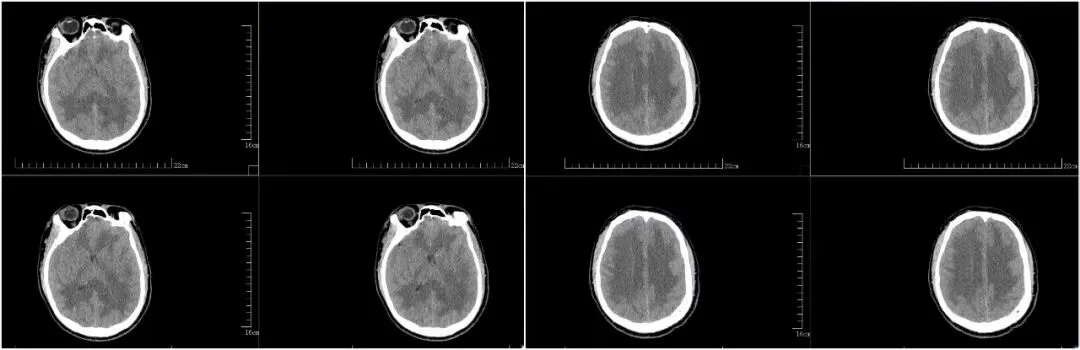

(小李脑部CT提示脑水肿)

入院检查评估显示,小李格拉斯哥昏迷评分仅6分,病情极其危重。低压低氧环境引发的严重脑水肿、肺水肿快速进展至呼吸衰竭,他随时面临呼吸心跳骤停、脑死亡、猝死风险,生死一线。